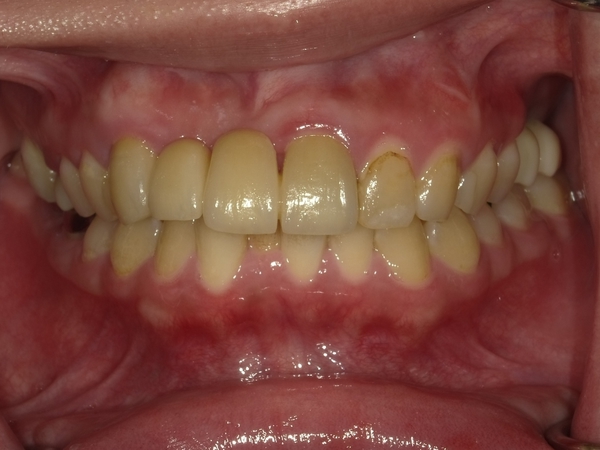

30代女性非抜歯

BEFORE→AFTER

〇ご相談内容:歯の叢生(ガタガタ)

〇矯正の種類:マウスピース型矯正「インビザラインGo」

〇治療期間:16週間

〇治療費用:44万円(税込)